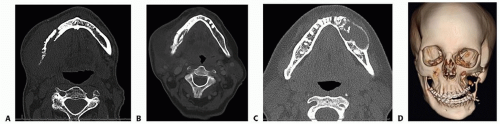

CAD/CAM virtual surgical planning can be used for acquired and congenital defects of the mandible. The most common cause of mandibular defects necessitating vascularized bone transfer is oncologic resection of the mandible for malignant tumors (FIG 2).

Fine cut (1-mm-thick sections) CT scans of the mandible and fibula with 3D reconstruction is the best option for examining the bone and for planning of the reconstruction. MR imaging may also be useful in some cases to evaluate the surrounding soft tissues but is not useful for developing 3D bone models (FIG 3).1,2

The CT scans of the mandible and fibula are used for preoperative virtual surgical planning with the oncologic surgeons, dentists (if necessary), and the reconstructive team.

It is important for the ablative surgeon to be involved in the planning session to accurately plan surgical margins. In cases where there is doubt about the surgical margins, two separate plans can be prepared. This approach enables intraoperative modification of the virtual surgical

plan depending on anatomic or oncologic findings. Thus, a “narrow” margin resection plan may be created as the initial plan; however, if intraoperative findings dictate larger resection, then the backup “wider” resection plan can be executed instead. This approach creates two separate cutting guides for the head and neck and fibula harvest plans (FIG 4A).